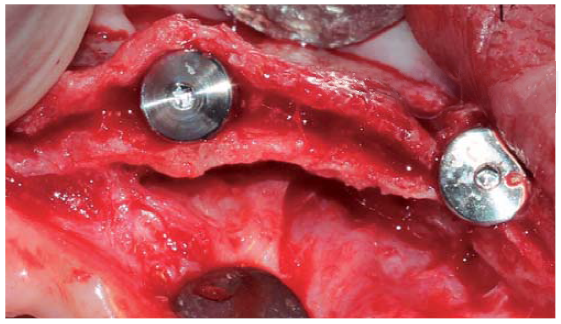

Se realizó una incisión supracrestal a espesor total, elevación del colgajo mucoperióstico exponiendo la tabla ósea hasta 4 mm de la cima de la cresta hacia vestibular y desde ese punto se dividió el colgajo a espesor parcial (Figura 3). Luego se marcaron los puntos de impacto en los sitios designados según la guía quirúrgica para la colocación de los implantes y se iniciaron las perforaciones con una fresa de 1.6 mm de diámetro para determinar el eje y profundidad deseada para los implantes. Luego se procedió a crear un surco a nivel crestal con un disco de diamante rompiendo el hueso cortical para crear el acceso a los escoplos al hueso esponjoso y con éstos se procede a separar las tablas óseas hasta llegar a una profundidad de 5 mm (Figuras 4 y 5). Seguidamente, se continuaron las perforaciones con una fresa de 2.0 mm de diámetro (Figura 6) y se realizó la expansión de la tabla vestibular creando una fractura en tallo verde con los expansores hasta alcanzar el diámetro del lecho óseo suficiente para poder utilizar la última fresa de 3.2 mm de diámetro (Figuras 7 y 8). Posteriormente, se colocaron los implantes a una velocidad de 25 rpm y a un torque de 35 Ncm (Figuras 9 y 10). Seguido de esto, se colocó un injerto óseo bovino particulado (Bonefill® Bionnovation Biomedical, Sao Paulo-Brazil), con la finalidad de preservar la integridad de las tablas óseas vestibulares (Figura 11). Todos estos procedimientos, se realizaron de la misma manera para la colocación de los seis implantes. Finalmente, se suturó con nylon monofilamento 5/0.